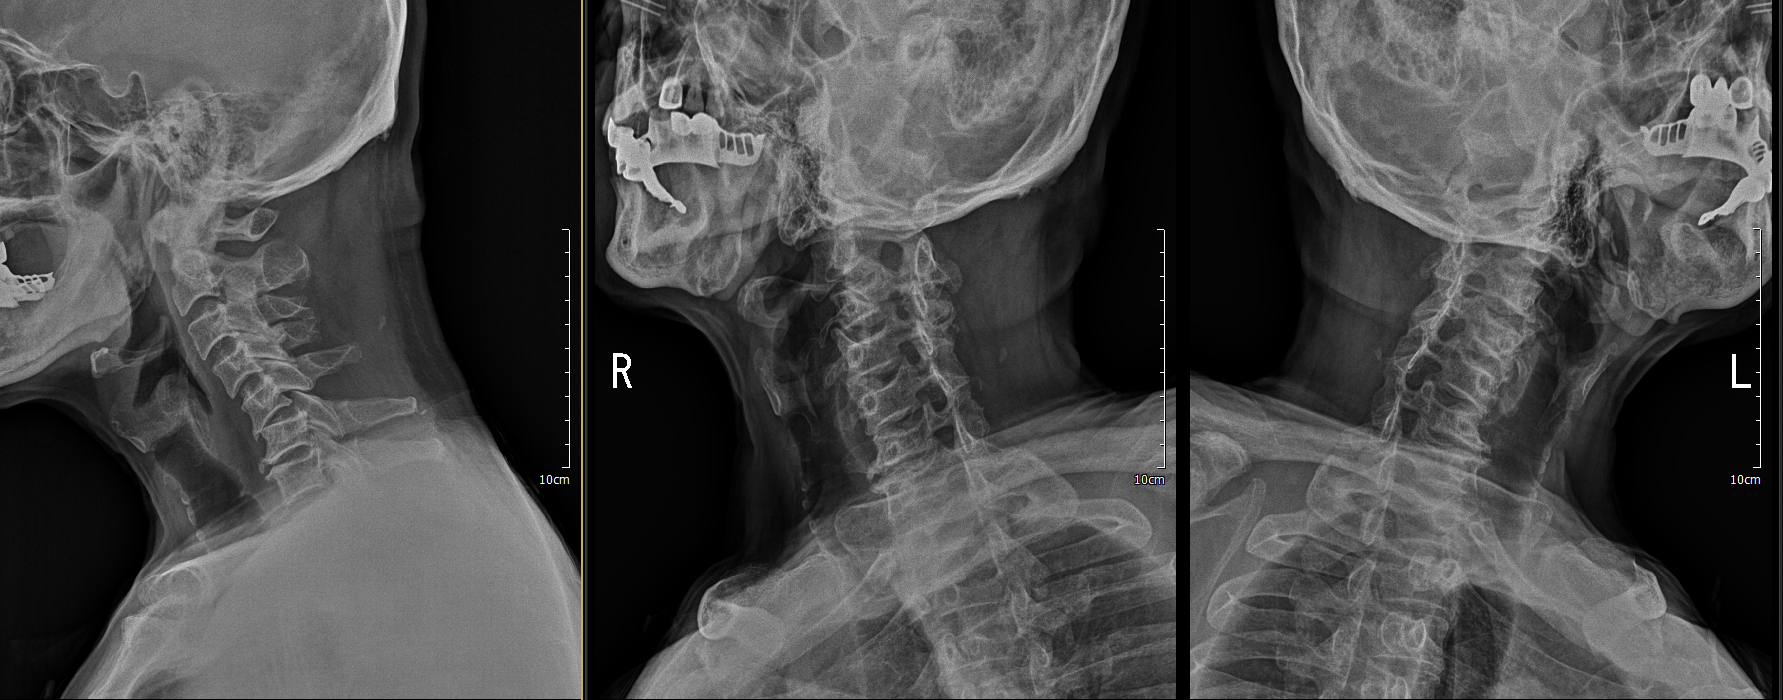

x ray 측면에서 보면 경추 5/6 후관절 탈골이 확인이 됨.